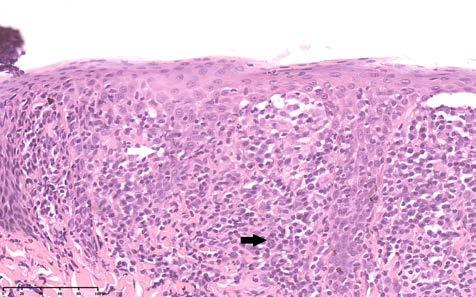

Figura 2. Linfoma epiteliotrópico en unión mucocutánea. Infiltración linfoide neoplásica en dermis superficial (flecha negra) y mostrando comportamiento epiteliotrópico (flecha blanca) (tinción hematoxilinaeosina, 30 x).

El estudio histopatológico por escisión de la trufa mostró hiperplasia epidérmica y una intensa infiltración dérmica superficial multifocal a difusa, conformada por células linfoides de tamaño medio, con anisocariosis moderada, escaso citoplasma y mitosis aisladas, observándose infiltración focal en la unión dermoepidérmica (epiteliotropismo) (Fig. 2). El diagnóstico presuntivo fue de linfoma epiteliotrópico. El estudio inmunohistoquímico evidenció una población linfoide CD3+, CD20-, fenotipo correspondiente a una población de linfocitos T, que confirmó el diagnóstico de linfoma epiteliotropo cutáneo asociado a fenotipo T (Fig. 3).

Figura 3. Linfoma epiteliotrópico en unión mucocutánea. Células neoplásicas de imagen anterior (Fig. 2) mostrando tinción positiva a CD3, infiltrando dermis superficial (flecha negra) y mostrando comportamiento epiteliotrópico (puntas de flecha negras) (tinción de linfocitos T mediante técnica inmunohistoquímica con anticuerpo anti-CD3 y contraste con hematoxilina, 30 x).